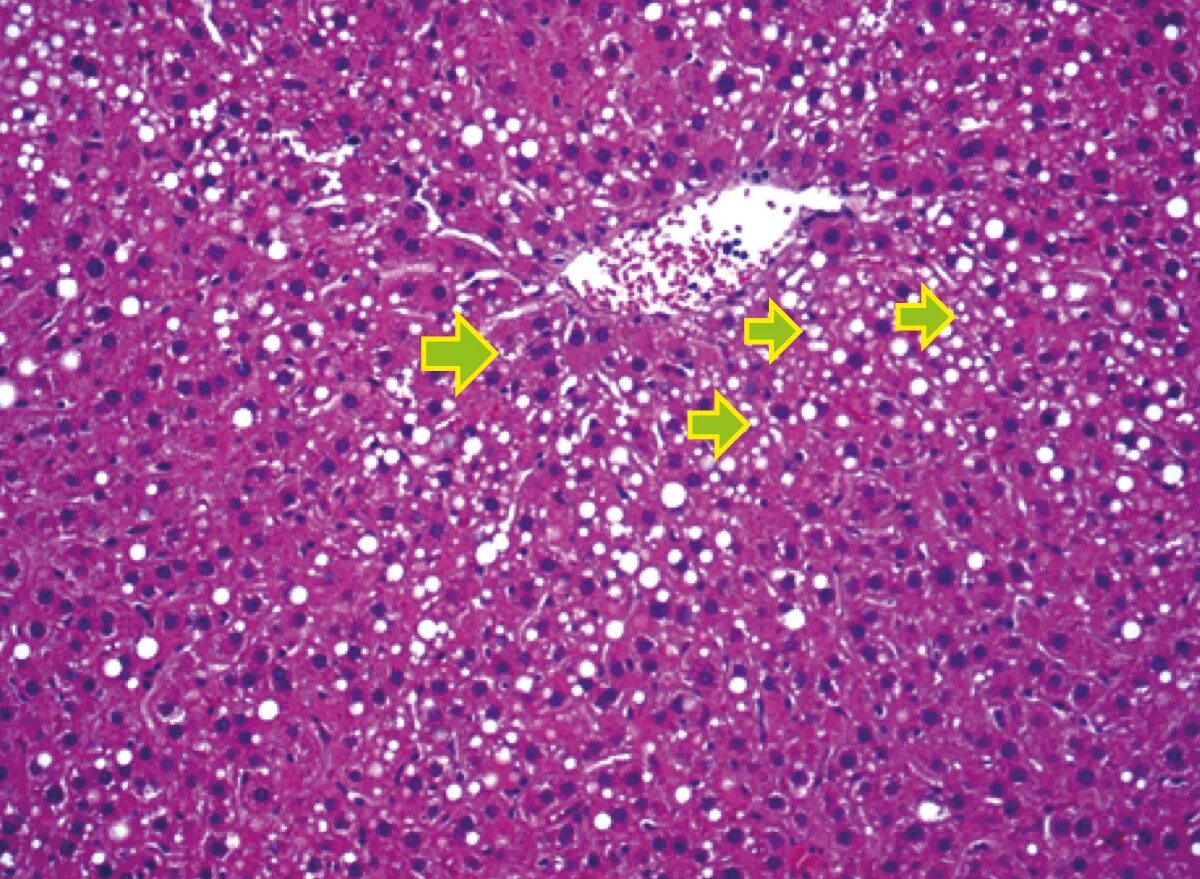

Гепатоциты человека